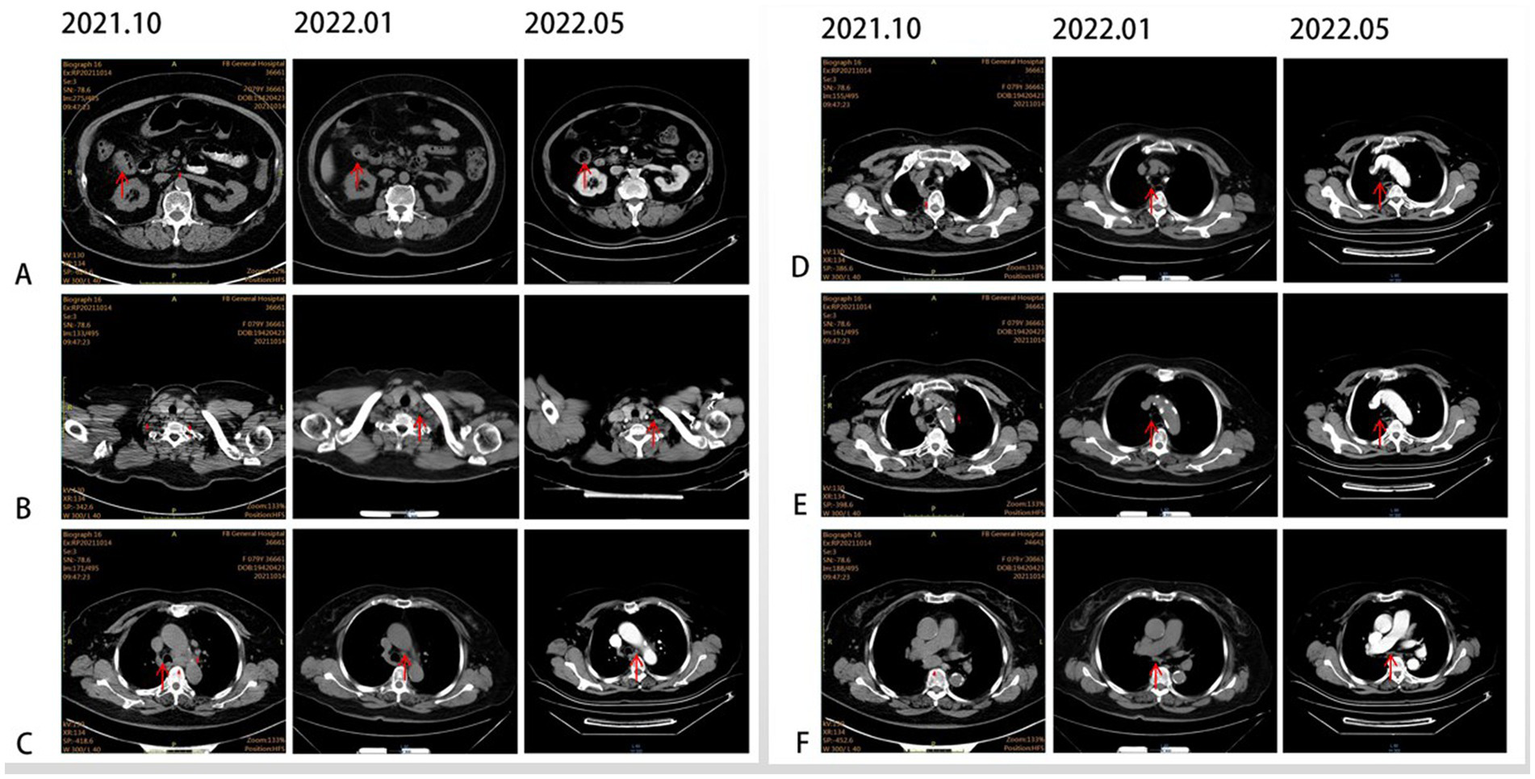

In October 2021, an 80-year-old woman with a history of hypertension, diabetes mellitus, and coronary artery stenting was admitted to our hospital with an enlargement of a left-sided supraclavicular lymph node. She had presented with multiple mediastinal lymph node metastases by whole-body positron emission tomography–computed tomography (PET-CT). The patient was diagnosed with advanced Colon adenocarcinoma located in the right hepatic flexure hemicolon by pathological diagnosis (Figure 1.1). Next-generation sequencing (the customized panel covering 1,267 cancer-related genes in Yucebio Technology using MGISEQ platform) revealed MSI-H, TMB-H (89.82Mut/Mb), BRAF V600E, DNMT3A D686Tfs*19, and MDM4 amplification from the lymph node metastasis. See the Supplementary material for more details about the 1,267-gene. Immunohistochemical (IHC) staining was negative for PD-L1 (Dako 22C3). Considering that the patient was MSI-H carrying multiple risk factors related to HPD, and MEK inhibitor plus cetuximab or panitumumab is used for BRAF V600E-positive CRC in the non-first-line setting. She was provided first-line treatment with a four-drug combination strategy consisting of sintilimab (200 mg), bevacizumab (300 mg), raltitrexed (3 mg), and oxaliplatin (130 mg), and the chemotherapy dose was halved in November 2021. The treatment records are shown in Figure 1. After one cycle of treatment, the patient showed a significant quick reduction in CEA (from 104.3 to 5.28 ng/ml) and CA199 (from 59.32 to 17.63 ng/ml), indicative of response to the combination regime (Figure 2). After four cycles of treatment, the primary tumor mass reduced in size, the enlarged lymph nodes gradually shrank, and the CEA and CA199 returned to normal values, with a clinical evaluation of partial remission (PR) (Figures 2, 3A–F). In addition to stomatitis, nausea, and fatigue (grade 1–2 adverse events), there were no other adverse effects reported. The patient agreed with our recommendation to take sintilimab (200 mg) combined with bevacizumab (300 mg) and raltitrexed (3 mg) every 21 days as maintenance therapy from April 2022. In May 2022, a PET-CT scan showed that the primary tumor disappeared (Figures 3A–F). The patient remained in remission until the last follow-up in Mar 2023 with the adverse events disappearing, and she had full compliance due to the great clinical response.

Figure 3

CT scans illustrating the changes in primary lesions and metastatic lymph nodes over time. (A) Primary lesion at the hepatic flexure (red arrow). (B) Supraclavicular lymph node (red arrow). (C) Tsubaortic lymph node (red arrow). (D) Paraesophageal lymph node (red arrow). (E) Retrotracheal lymph node (red arrow). (F) Subcarinal lymph node (red arrow).